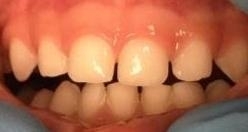

The lip tie was released on an 11 month infant.  One year later you can start to see the gap between the front teeth close. Although the tie was released for other issues, you can see the alignment of a child's front teeth change, especially if done before the canines erupt.